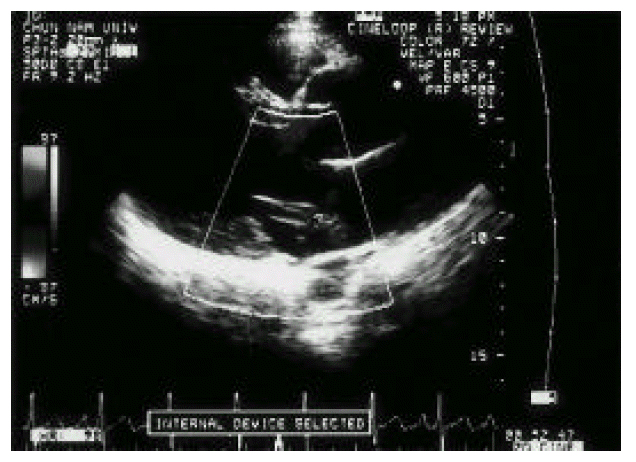

An electrocardiogram revealed no abnormalities except for a sinus tachycardia at a rate of 112. A radiograph of the chest was normal. Both hand AP roentgenogram showed arachnodactyly (Fig. 2). A radiograph of spine showed no scoliosis and kyphosis. An echocardiogram revealed the prolapse of posterior mitral leaflet and mitral regurgitation, but not aortic regurgitation and dissection (Fig. 3). Peripheral blood smear showed markedly increased blasts and decreased platelet count. Findings on bone marrow examination showed that most of the nucleated cells were monoblasts (Fig. 4a) that were negative on myeloperoxidase and chloracetate esterase staining but demonstrated positivity on staining with non-specific esterase (Fig. 4b). Immunophenotype of those cells showed CD13+, CD33+, CD56+ and HLA-DR+. Cytogenetic studies on the marrow showed 46 XY. He was diagnosed as acute monoblastic leukemia (M5a).

Fig. 3.

Echocardiogram (left parasternal long axis view) showing the prolapse of posterior mitral leaflet and mitral regurgitation.